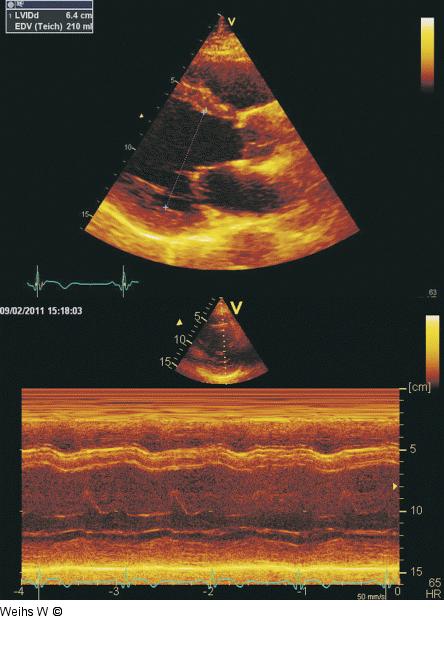

Abbildung 2: Parasternaler Längsschnitt - M-Mode Parasternaler Längsschnitt und M-Mode zur Messung der enddiastolischen Duchmesser des linken Ventrikels. Diese sollten nur in Ausnahmefällen herangezogen werden, wenn die Bestimmung der Volumina (siehe Abb. 1) nicht möglich ist. Die Umrechung der Durchmesser in Volumina (Teichholz-Formel) ist nicht zulässig. |

Abbildung 2: Parasternaler Längsschnitt - M-Mode

Parasternaler Längsschnitt und M-Mode zur Messung der enddiastolischen Duchmesser des linken Ventrikels. Diese sollten nur in Ausnahmefällen herangezogen werden, wenn die Bestimmung der Volumina (siehe Abb. 1) nicht möglich ist. Die Umrechung der Durchmesser in Volumina (Teichholz-Formel) ist nicht zulässig. |